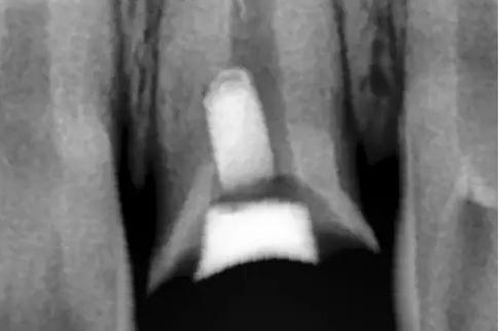

用MTA修補(bǔ)術(shù)后觀

術(shù)后X片